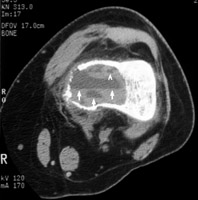

Single axial section of a knee CT which reveals an aneurysmal bone cyst in the left distal femur with a fluid-fluid level. The fluid-fluid level sign is by no means pathognomonic, but is helpful in narrowing the differential. The sign is produced by a cystic lesion with water density fluid layering atop blood. The fluid-fluid level is often seen in aneurysmal bone cysts; but it may also be seen in giant cell tumor, telangiectatic osteosarcoma, and chondroblastoma.

CT femur - Click on the image for a larger version